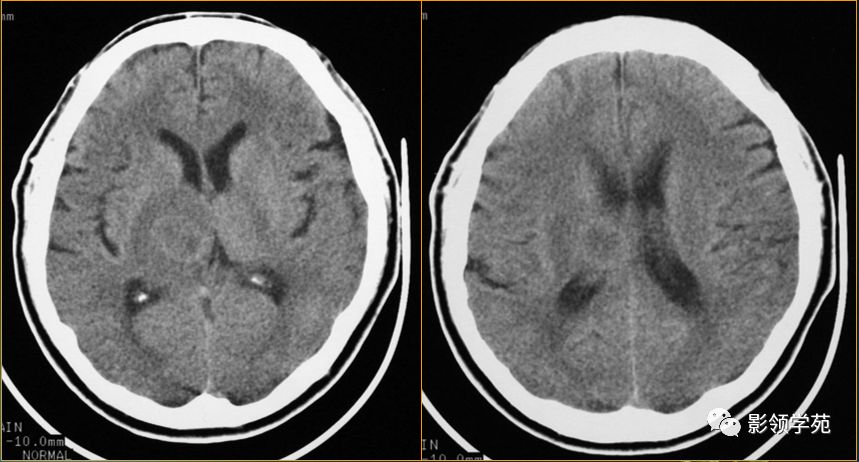

脑脓肿与脑结核的影像表现